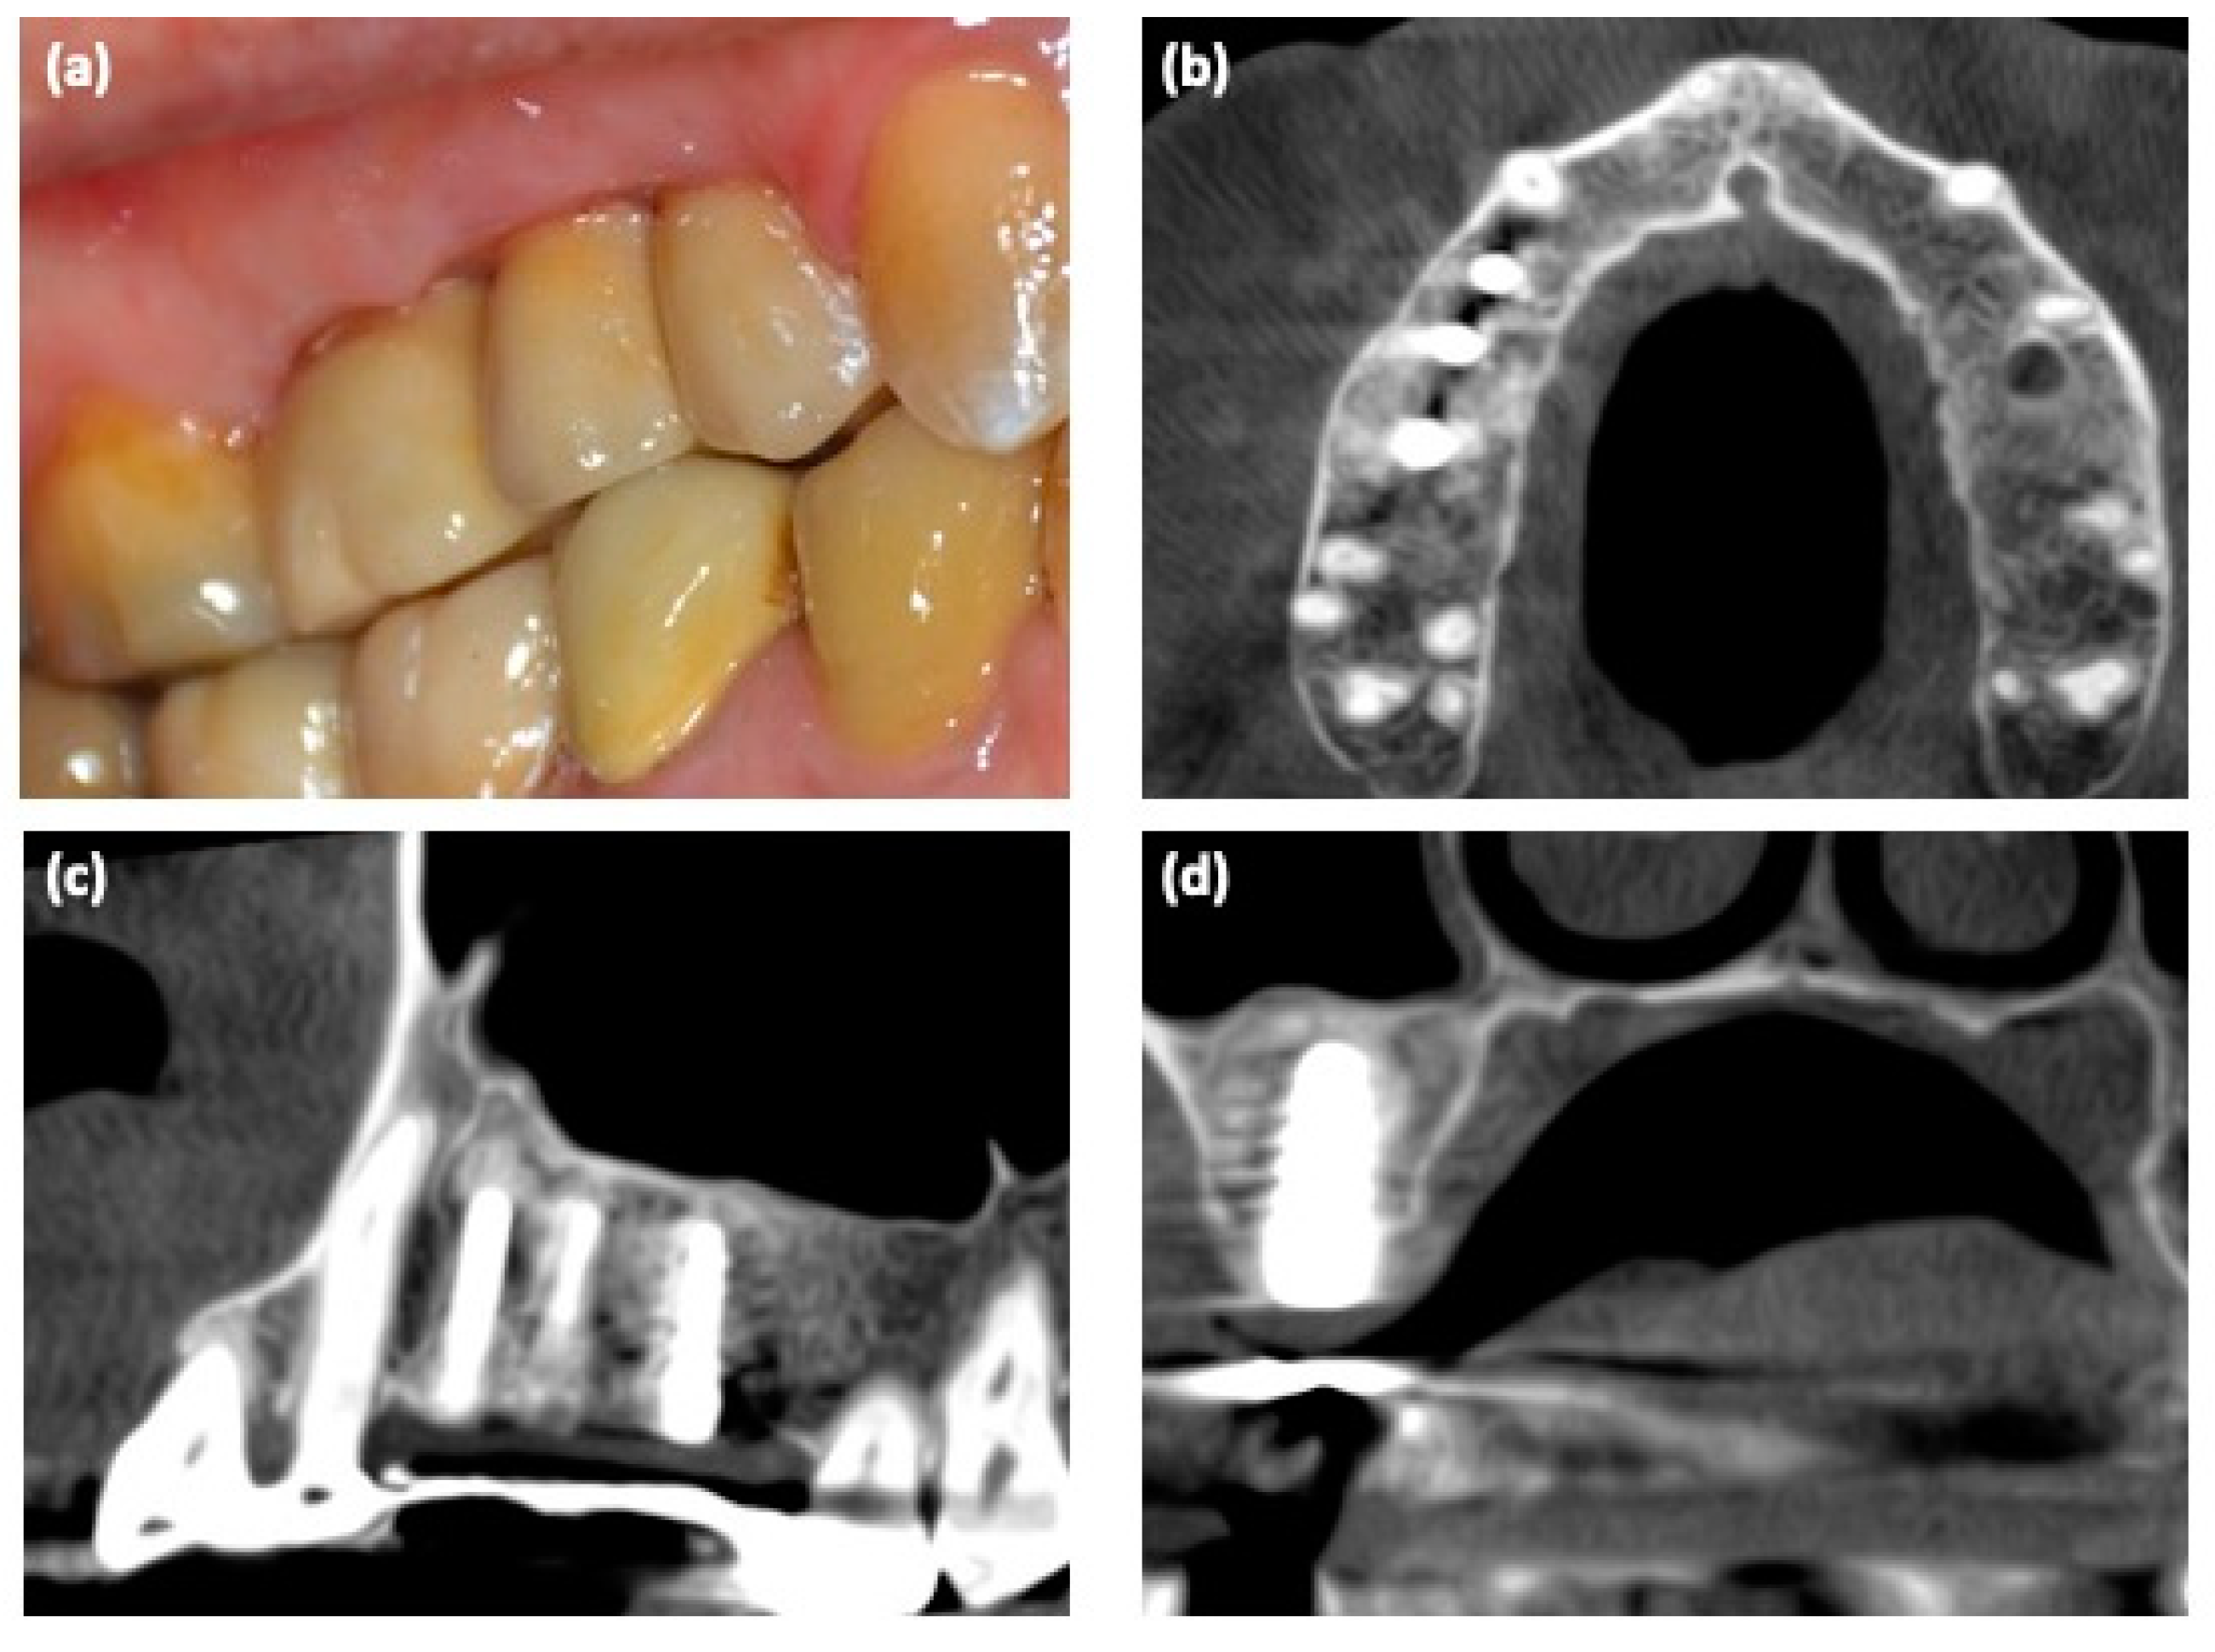

Three months after the implant placement, an impression was made; implants were loaded with screw-retained temporary fixed partial restorations. Definitive restoration was placed after 2 months (Figure 4a). The regeneration of bone tissue was highlighted with a new CBCT (Figure 4b–d).

Figure 4. (a) Clinical view of the implant-based rehabilitation; (bd) 3D CBCT scan after implant placements.